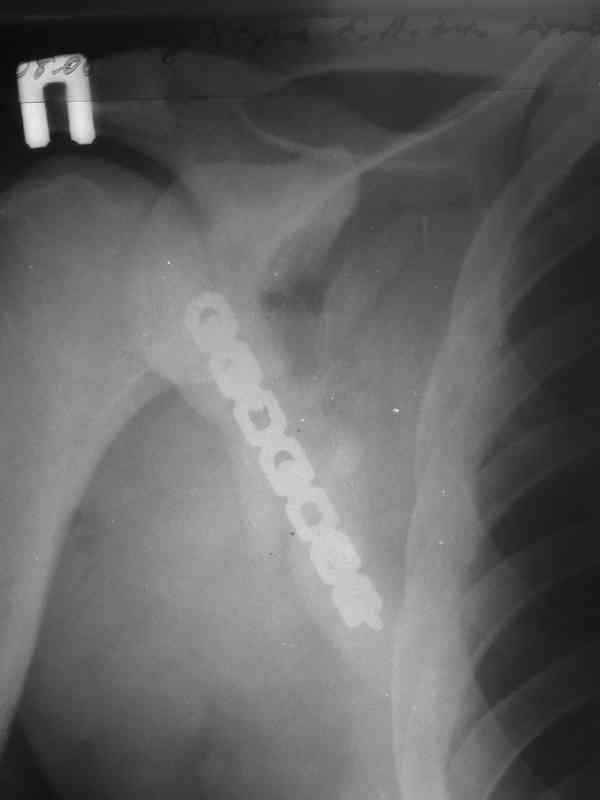

Мы в таких случаях оперируем в 2-а этапа:

1. Стабилизация грудной клетки(фиксируем ребра по одной из линий рекон. LCP)

2. Остеосинтез лопатки из заднего доступа(рекон.LCP, LC-LCP 3,5мм, Т-обр.LCP 3,5мм); ключицу стандартно